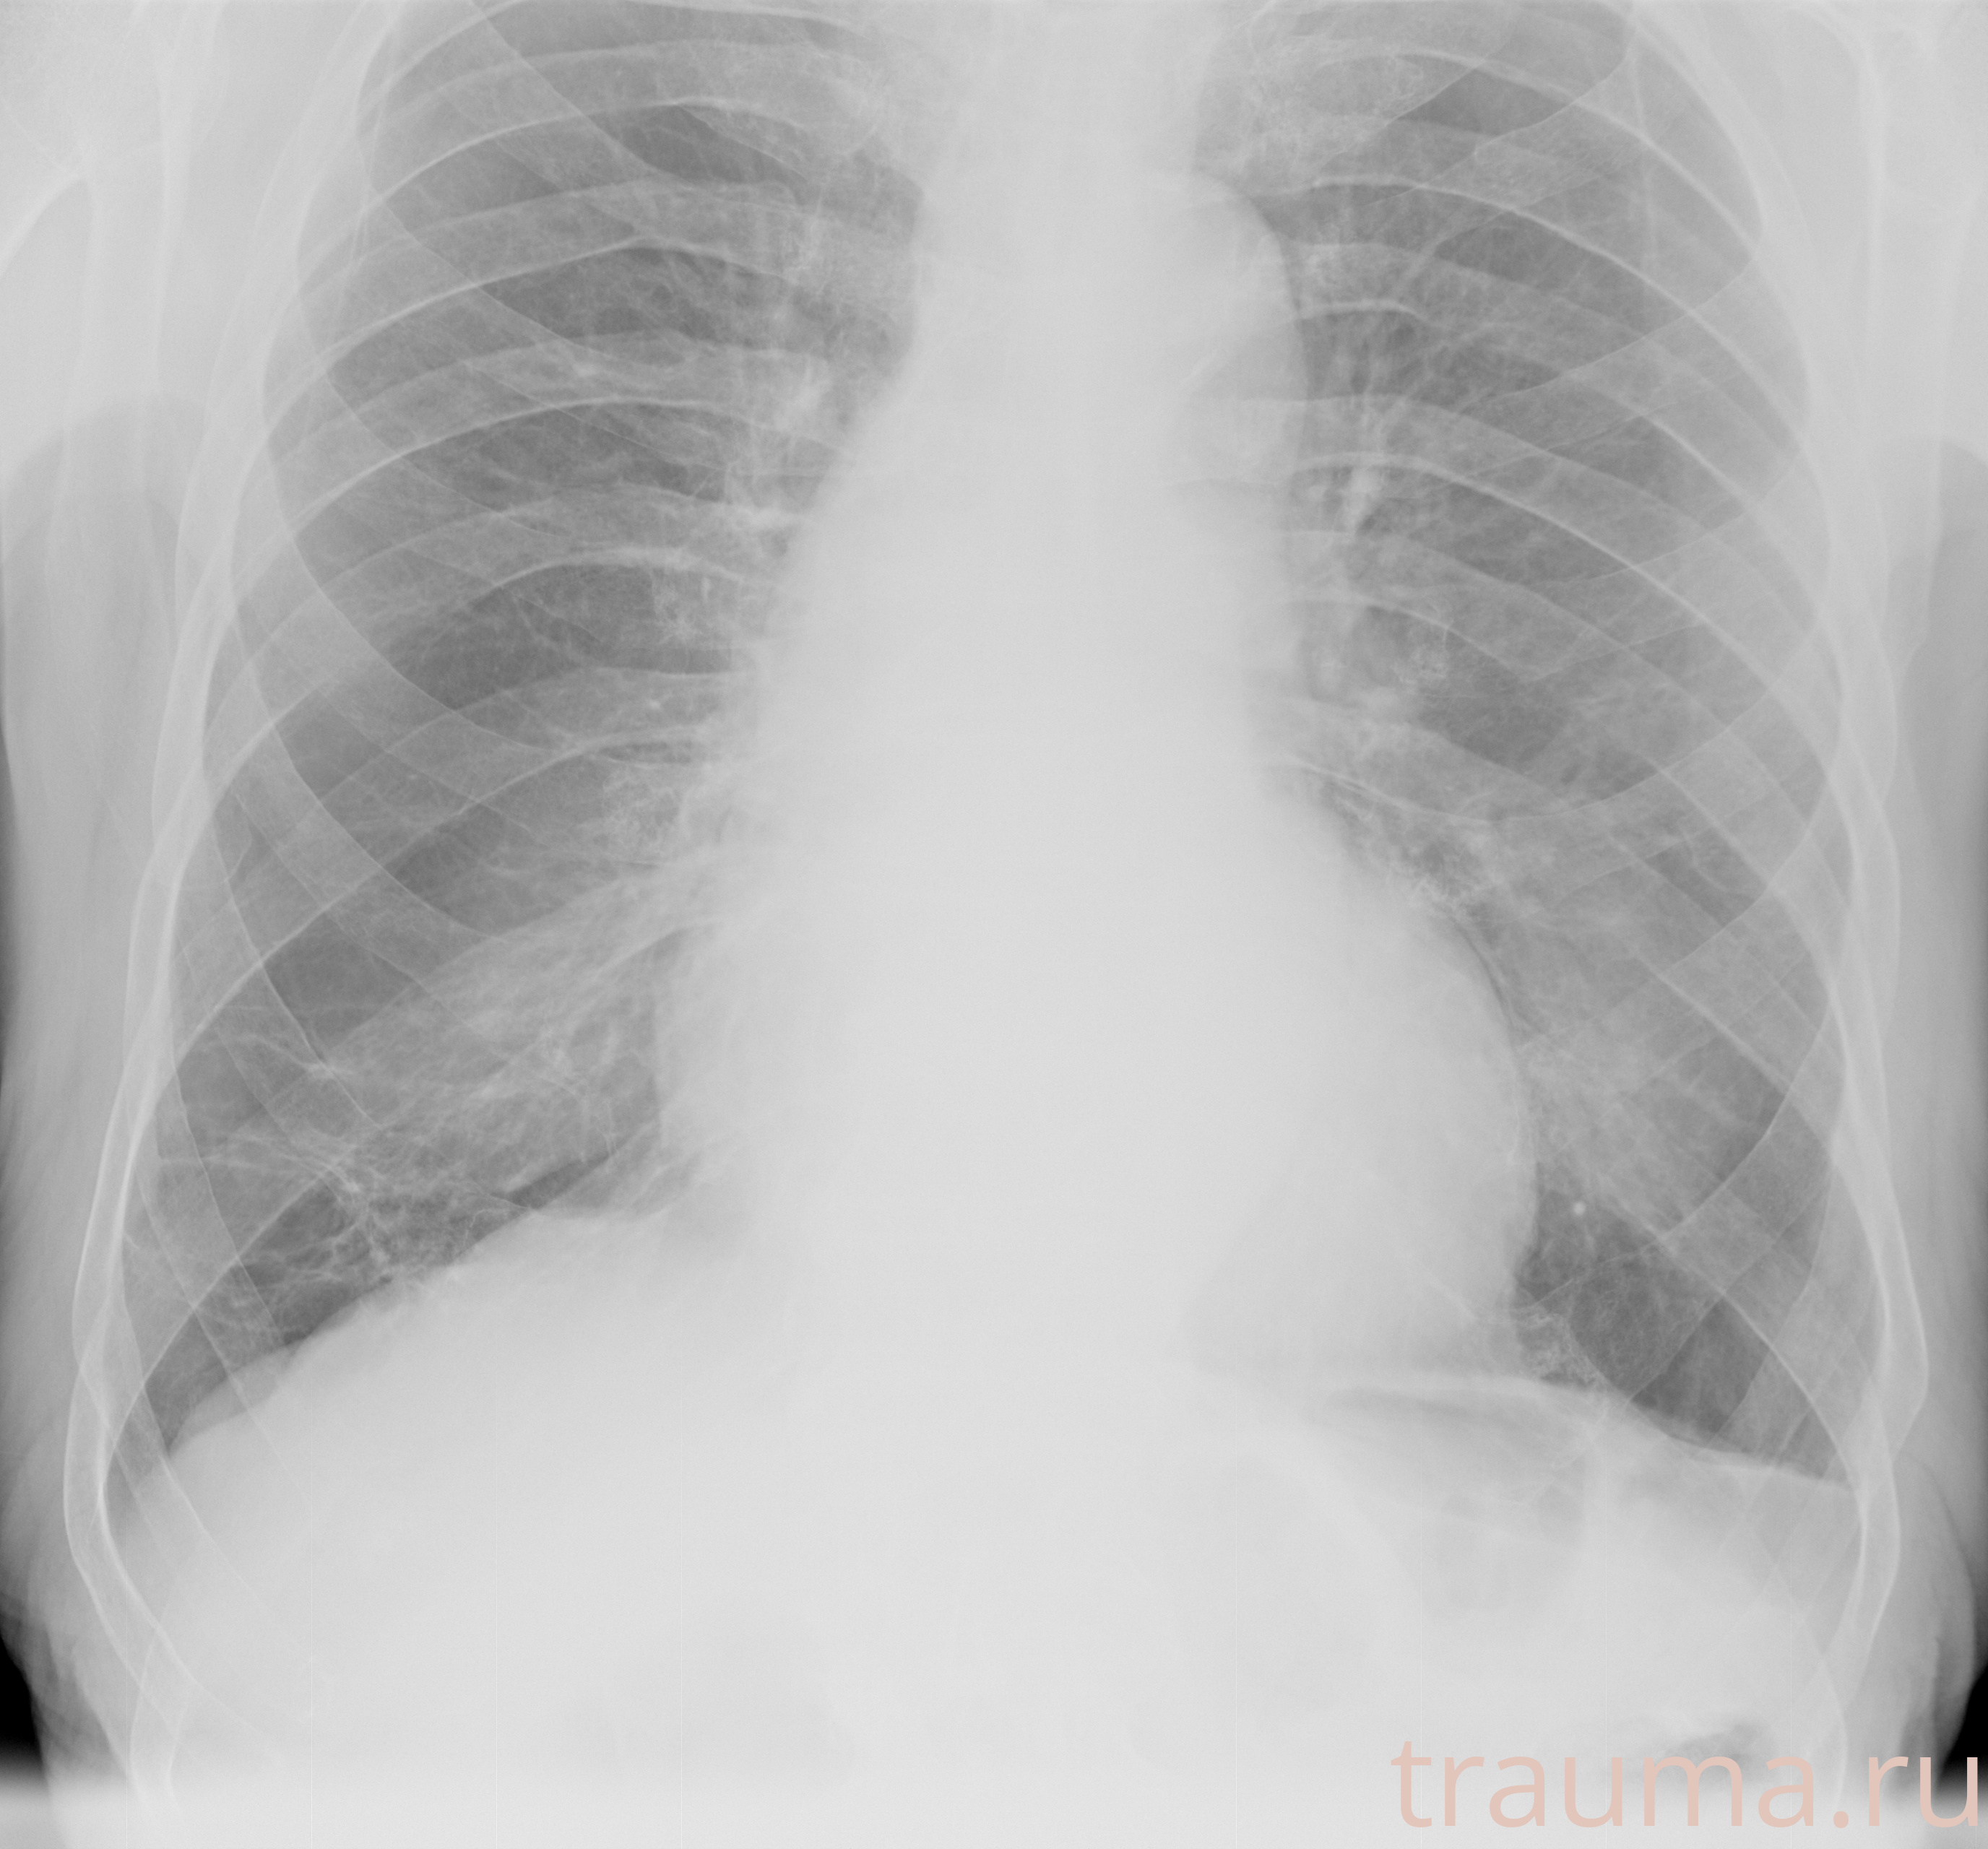

Рентген на дому: по вашему адресу приезжает врач-рентгенолог, травматолог-ортопед с мобильным рентгеновским аппаратом, проводит диагностику травмы или заболевания, делает необходимые рентгенограммы, дает рекомендации по дальнейшему лечению. Получить качественные снимки в домашних условиях возможно благодаря уникальной методике, разработанной МосРентген Центром для института  Склифосовского

при переломе шейки бедра и пневмонии от компании МосРентген Центр - партнера Института имени Склифосовского